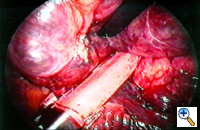

Group I: Single large bulla with normal underlying lung (Figure 1)

| Figure 1: Operative view at thoracotomy of a single bulla with normal underlying lung. | Figure 2: Operative view at thoracotomy of multiple bullae with underlying lung with diffuse emphysema. |